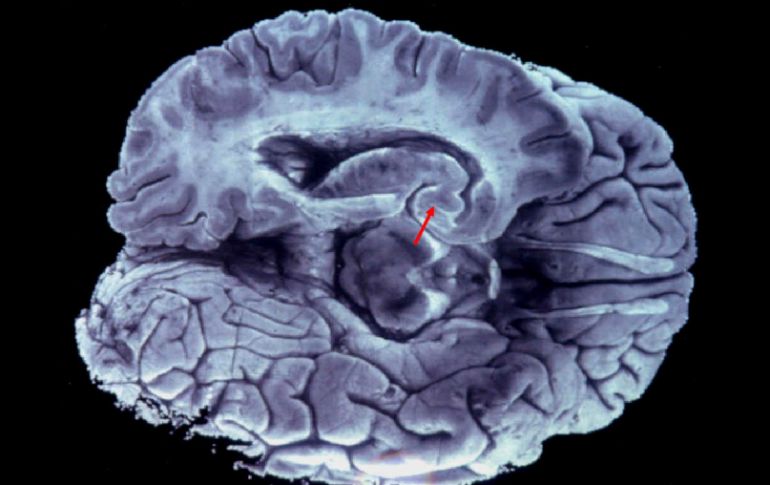

Tecnología | Este avance supone un paso más hacia la creación de un cerebro biónico Desarollan nanomemoria que almacena datos como un cerebro humano Este avance supone un paso más hacia la creación de un cerebro biónico Por: SUN 12 de mayo de 2015 - 08:57 hs La eventual creación de un cerebro biónico contribuirá a entender mejor enfermedades como el Alzheimer. EFE / ARCHIVO SÍDNEY, AUTRALIA (12/MAY/2015).- Científicos australianos desarrollaron una nanomemoria que es capaz de almacenar información de la misma manera que un cerebro humano, lo que supone un paso más hacia la creación de un cerebro biónico, informaron medios locales. El aparato, que es diez mil veces más delgado que un cabello humano, imita la compleja ingeniería del cerebro con su retorcida masa de las vías nerviosas, según el equipo de la Universidad RMIT de Melbourne que lo ha creado. "El desarrollo de estas celdas de nanomemoria era un requisito previo para la construcción de redes de neuronas artificiales que sean capaces de equiparar la actuación y las características de sus pares biológicos", dijo el líder de la investigación, Hussein Nili, a la cadena ABC. A diferencia de los aparatos de almacenamiento digital, como los USB que registran los datos en secuencias binarias, la celda de nanomemoria puede almacenar la información en múltiples estados porque es análoga, explicó el científico. Nili comparó sus diferencias a un interruptor de electricidad que puede encender y apagar la luz, con otro que puede graduar la intensidad de la misma. La nanomemoria puede "dar mayor flexibilidad en términos de la información que se desea almacenar y las características que se pueden obtener", añadió. La eventual creación de un cerebro biónico contribuirá a entender mejor las características de los seres humanos respecto a las enfermedades como el Parkinson o el Alzheimer e incluso para reemplazar en un futuro lejano las partes dañadas en este delicado órgano. Por su lado Sumeet Walia, coautor de este trabajo publicado en la revista Advanced Functional Materials, dijo que el aparato puede servir para desarrollar formas de inteligencia artificial capaces de almacenar, recordar y rememorar eventos pasados. Temas Estudios científicos Australia Investigación científica Ciencia médica Cerebro Lee También NASA confirma si el cometa 31/ATLAS amenaza la vida en la Tierra o no Detalles sobre la esquizofrenia, la experiencia de "voces" internas Conmociones cerebrales, la cuarta lesión más frecuente en partidos de la Conmebol Estudio chino revela una mutación que eleva riesgo de alzhéimer Recibe las últimas noticias en tu e-mail Todo lo que necesitas saber para comenzar tu día Registrarse implica aceptar los Términos y Condiciones